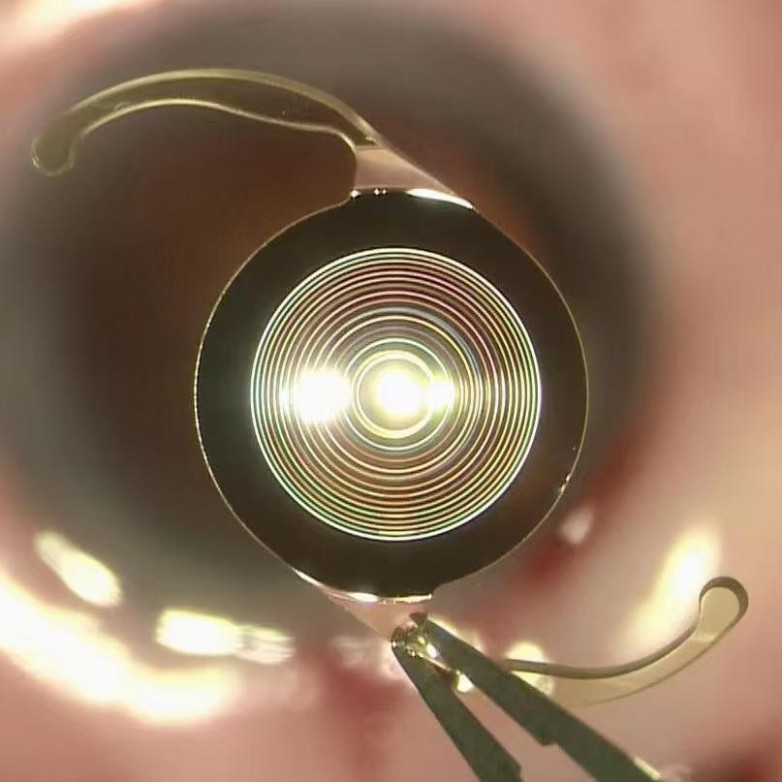

11月25日,在蔡司ARTEVO800数字导航3D显微镜的辅助下,王建文教授成功为李女士植入全新疏水性材质三焦点人工晶状体。术后一周复查时,她的远、中、近裸眼视力均达到1.2。“手术第二天就能看清楚远处,中距离的电脑屏幕,连手机小字也一目了然,真的太神奇了!我现在就像是换了一双‘新眼睛’一样。”李女士欣喜地说道。

据了解,全新疏水性材质三焦点人工晶状体在光学设计与材质上均实现重大突破。这款人工晶状体有高达88%的光能利用率,术后对比敏感度高,视觉质量好,减少了闪辉、眩光和光晕等视觉干扰,视物更舒适。通过专有的ENLIGHTEN“焕能”光学技术,中焦点位于60cm的设计,比传统的80cm更加贴近日常生活用眼。

在材质方面,其采用疏水性丙烯酸酯材质,具有优异的生物相容性,搭配后表面连续直角方边设计,有助于减少后发性白内障的发生率,为患者提供更优质的视觉质量。